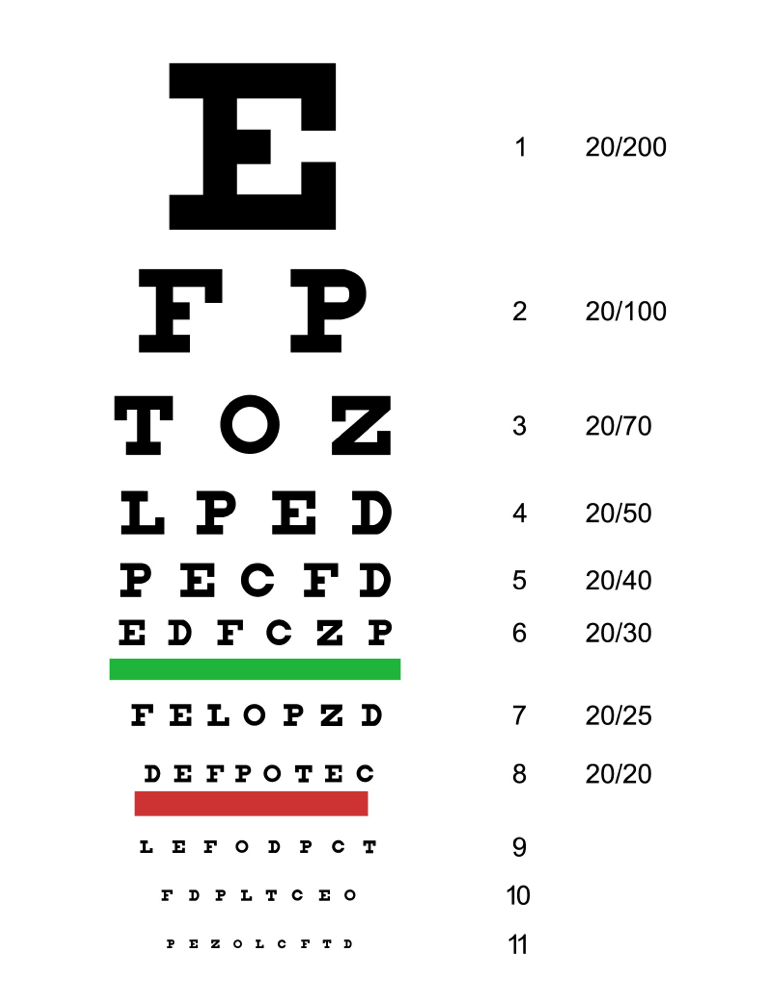

Gründliche Untersuchung der Augen

Das Hauptsymptom der AMD ist eine Beeinträchtigung des Sehvermögens. Daher wird die AMD häufig im Rahmen einer routinemäßigen Augenuntersuchung diagnostiziert. Bei einer umfassenden Untersuchung der Sehschärfe wird die Fähigkeit einer Person gemessen, Details, Formen und Buchstaben in einer bestimmten Entfernung zu sehen.3 Die bestkorrigierte Sehschärfe (BCVA) wird in der Regel anhand des Snellen-Sehtests ermittelt. Alternativ kann Ihre medizinische Fachkraft aber auch andere Tafeln verwenden. Die Anzahl der Buchstaben, die eine Person richtig erkennen kann, entspricht ihrer Sehschärfe. Mit anderen Worten: Je weiter unten auf der Snellen-Tafel eine Person lesen kann, desto besser ist ihre Sehschärfe.3